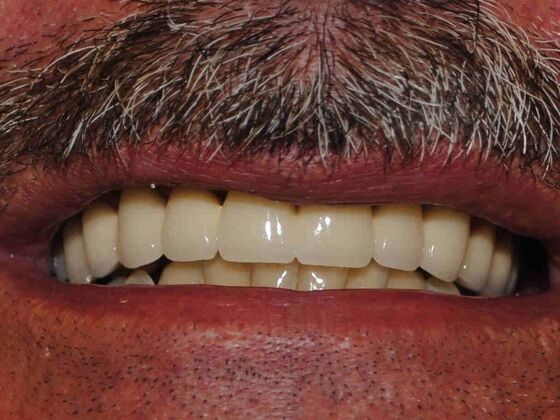

At Lamendola Dentistry, we are committed to exceeding patients' expectations. We offer relaxing amenities and complete continuing education to stay up to date on the latest techniques. Dr. Louie Lamendola is affiliated with prominent dental organizations like the: